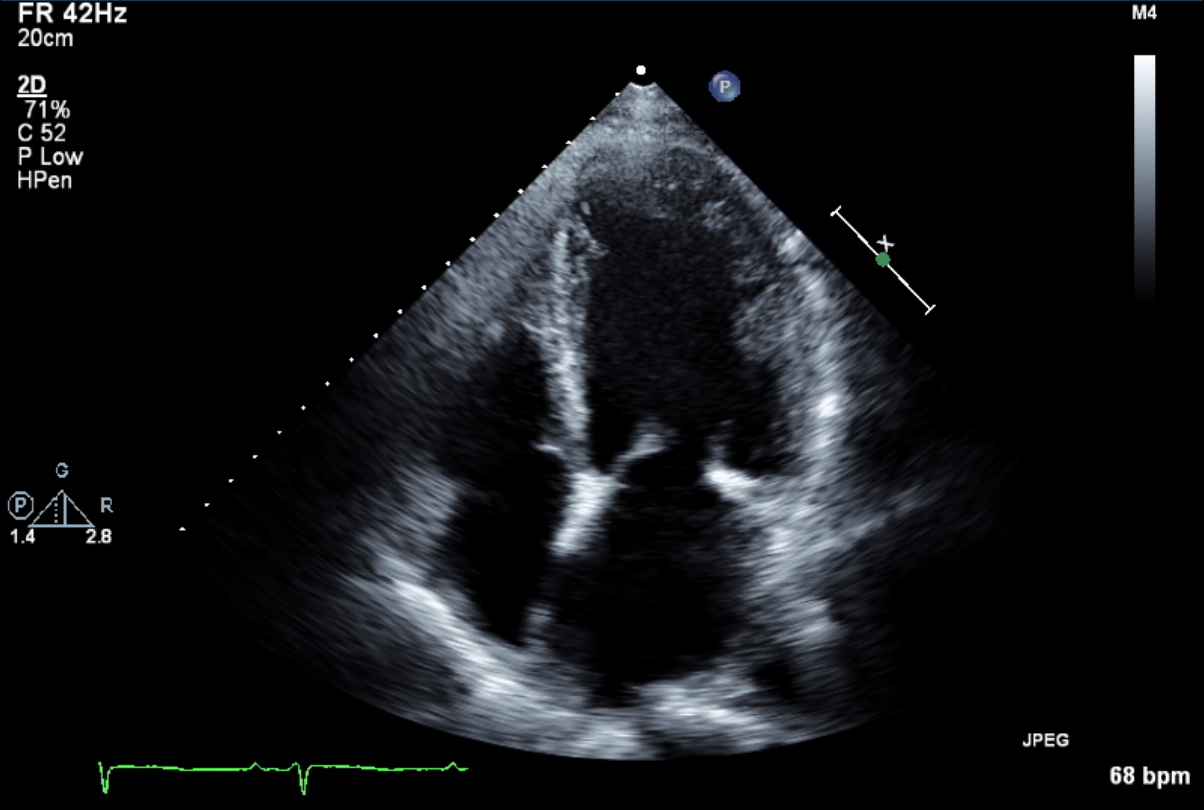

| 超音波検査 |

超音波装置を用いて、心臓や腹部(肝臓・胆のう・膵臓・腎臓・脾臓・膀胱など)、血管の状態を観察します。腹部エコー検査は空腹で行います。